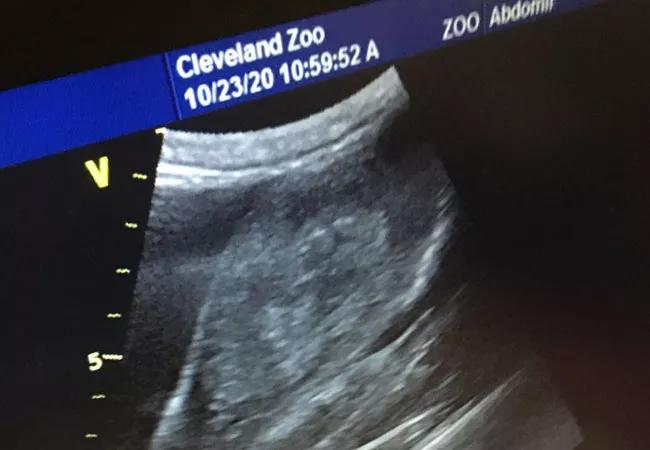

Veterinarians from the Cleveland Metroparks Zoo were concerned about the health of Freddy, a 230-pound, 46-year-old female gorilla, when they called Dr. Peskin to ask him to take a look. Given Dr. Peskin’s skill and experience, the Zoo team asked to collaborate on the procedure. Knowing he would need assistance, Dr. Peskin brought his mentee, Catherine Caponero, DO, along to conduct an ultrasound.

“We were able to confirm the presence of a mass on the uterus and, after biopsy, we were concerned about possible malignancy,” says Dr. Peskin.